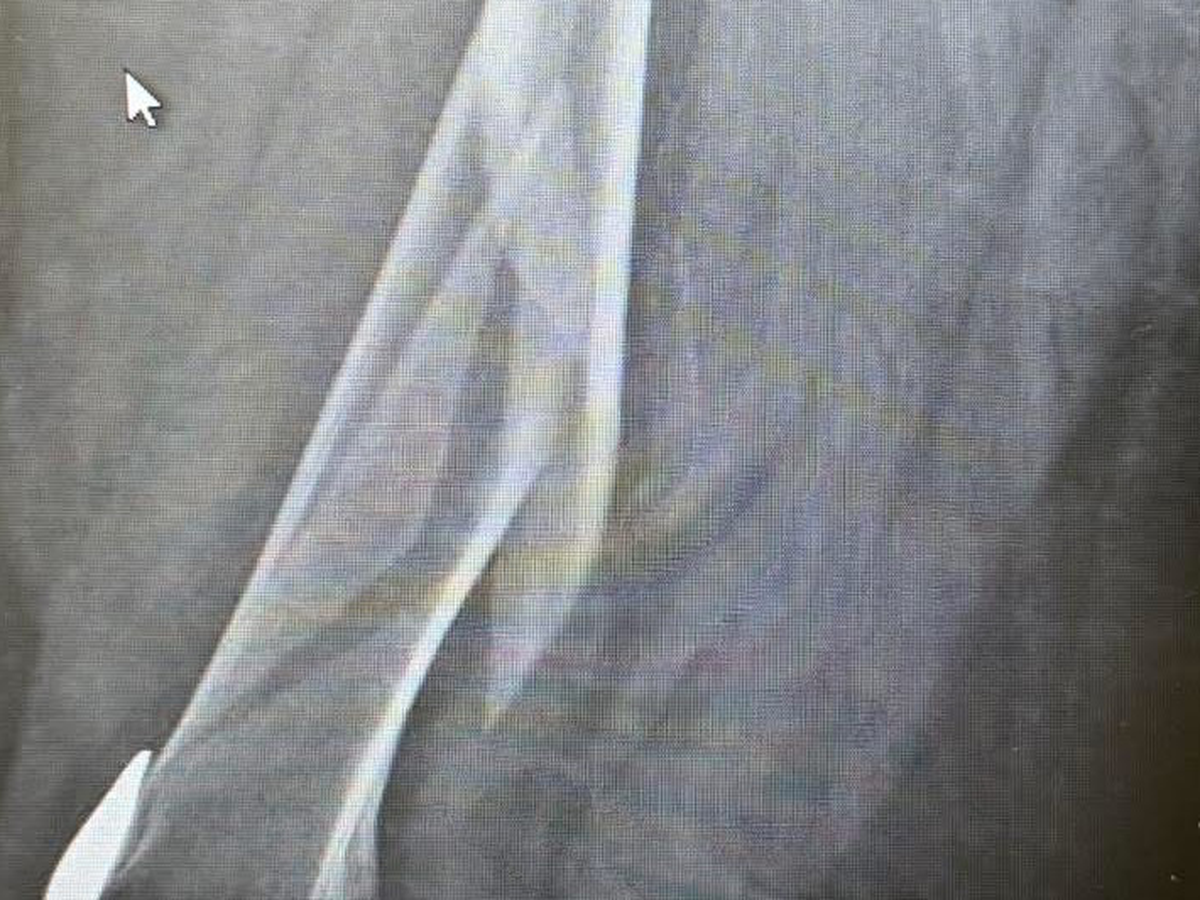

I never thought I would be in a position to have to ask for help, but I recently fell on December 9th and broke my femur, requiring immediate surgery to repair it. Since then, I have gone from the hospital to a rehab facility to get my strength back.